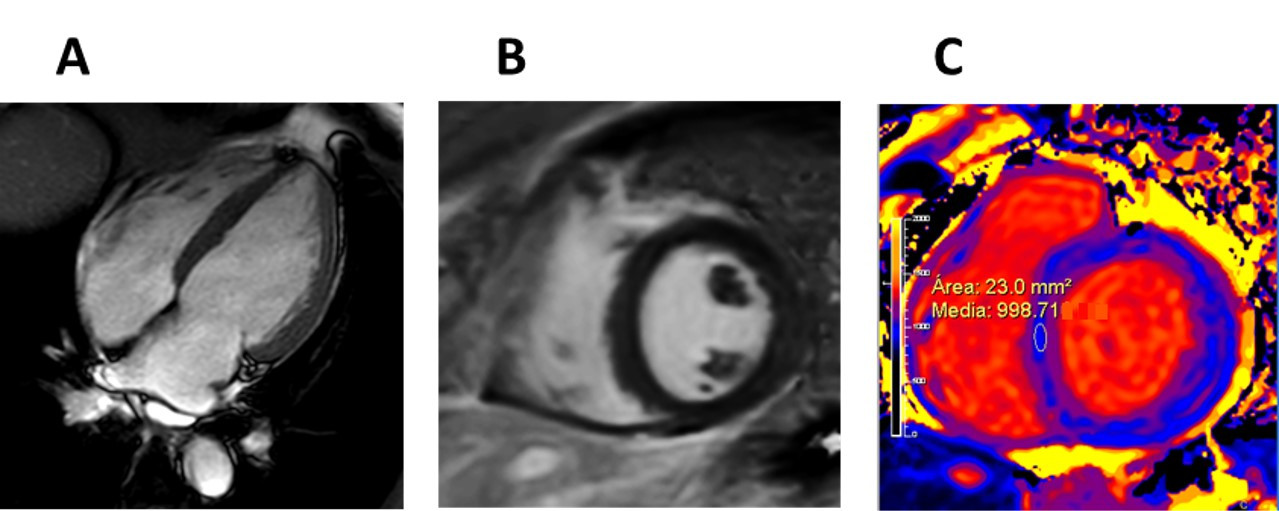

Fig. 6.Early stage Fabry disease. (A) Four-chamber cardiac magnetic resonance (CMR) image of a patient with early stage Fabry disease showing no left ventricular hypertrophy. (B) Short-axis late gadolinium enhancement CMR image demonstrating no late gadolinium enhancement. (C) Short-axis CMR T1 colour map demonstrating reduced T1 signal.

Fig. 7.Late stage Fabry disease. (A) Four-chamber cardiac magnetic resonance (CMR) image of a patient with late stage Fabry disease showing severe concentric left ventricular hypertrophy. (B) Short-axis late gadolinium enhancement (LGE) CMR image demonstrating extensive LGE in the basal inferolateral wall (arrow).